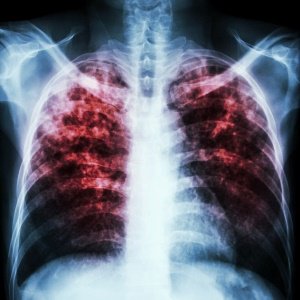

مرض السل - Tuberculosis